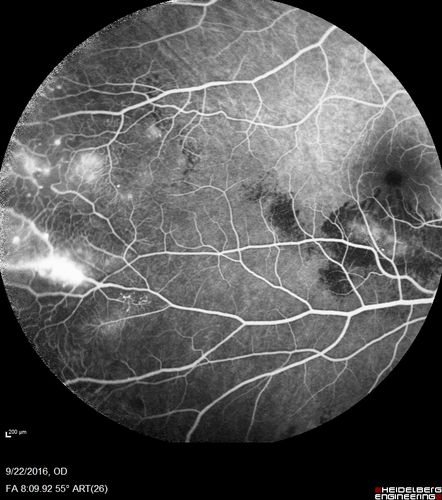

Coats' Disease - 14 year old - Asymptomatic

Presented with macular exudates. Temporal macroaneurysms responded to laser. Ultra-wide field FA shows nonperfusion